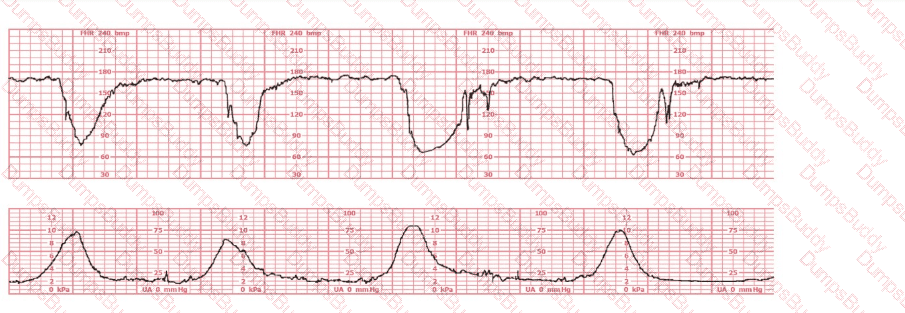

A woman at 39-weeks gestation is in early labor, 2–3 cm dilated, 85% effaced, and –2 station. Based on the fetal heart rate tracing shown, what is the most appropriate first intervention?

The decelerations seen in the fetal monitoring tracing shown are best described as: